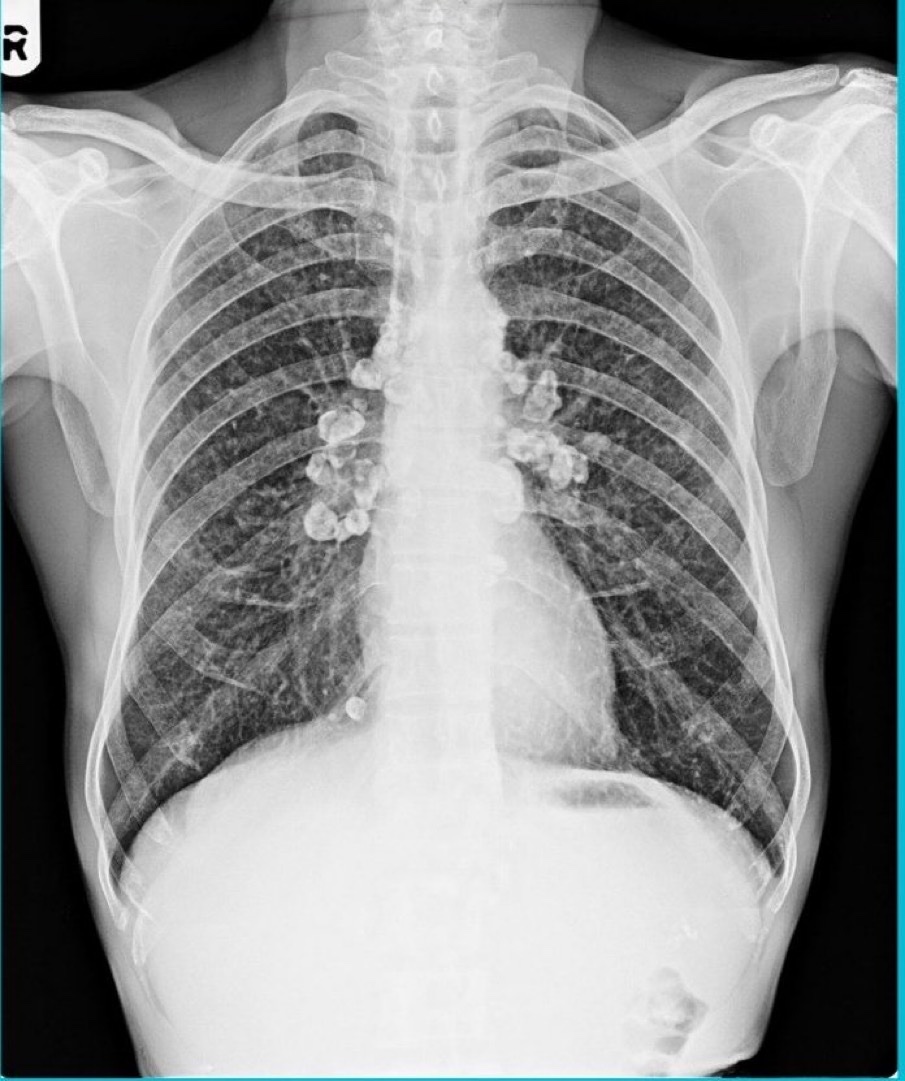

A middle aged man who worked as a sandblasting worker for many years p/w chronic cough, fatigue & exertional dyspnea. CXR showed these findings. What is the likely diagnosis? #MedEd #MedTwitter

BrownJHM's tweet image. A middle aged man who worked as a sandblasting worker for many years p/w chronic cough, fatigue & exertional dyspnea. CXR showed these findings. What is the likely diagnosis? #MedEd #MedTwitter